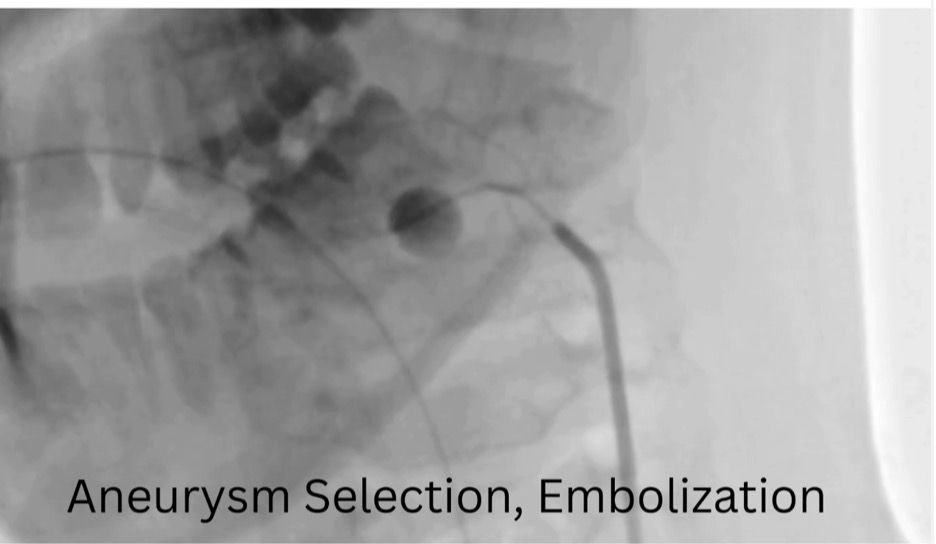

ومن جانبه، ذكر الدكتور احمد كمال المدير التنفيذي للمستشفيات الجامعية، أنه تم تجهيز وحدة القسطرة على الفور، حيث نجح الفريق الطبي في غلق التمدد الشرياني باستخدام حلزونات دقيقة عبر القسطرة التداخلية، مما أسهم في السيطرة الكاملة على النزيف دون الحاجة إلى جراحة تقليدية، وتقليل احتمالات المضاعفات.